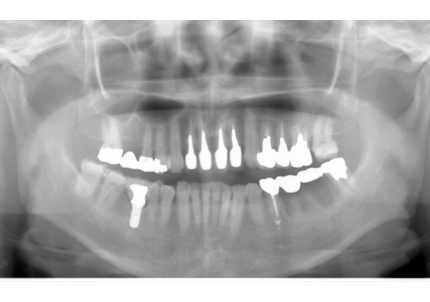

18.インプラント埋入後 パノラマレントゲン